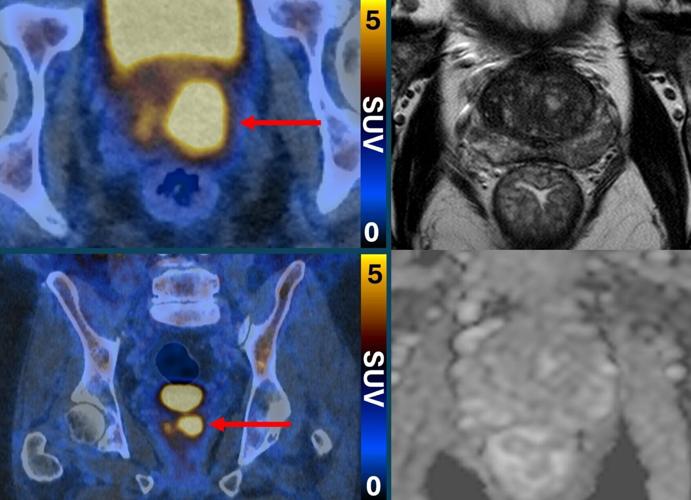

Glowing prostate cancer cells PSMA PET 2. (PRIMARY 2 via SWNS)

Clinically significant prostate cancer (left, PSMA PETCT) despite normal MRI (right, MRI). (PRIMARY2 via SWNS)